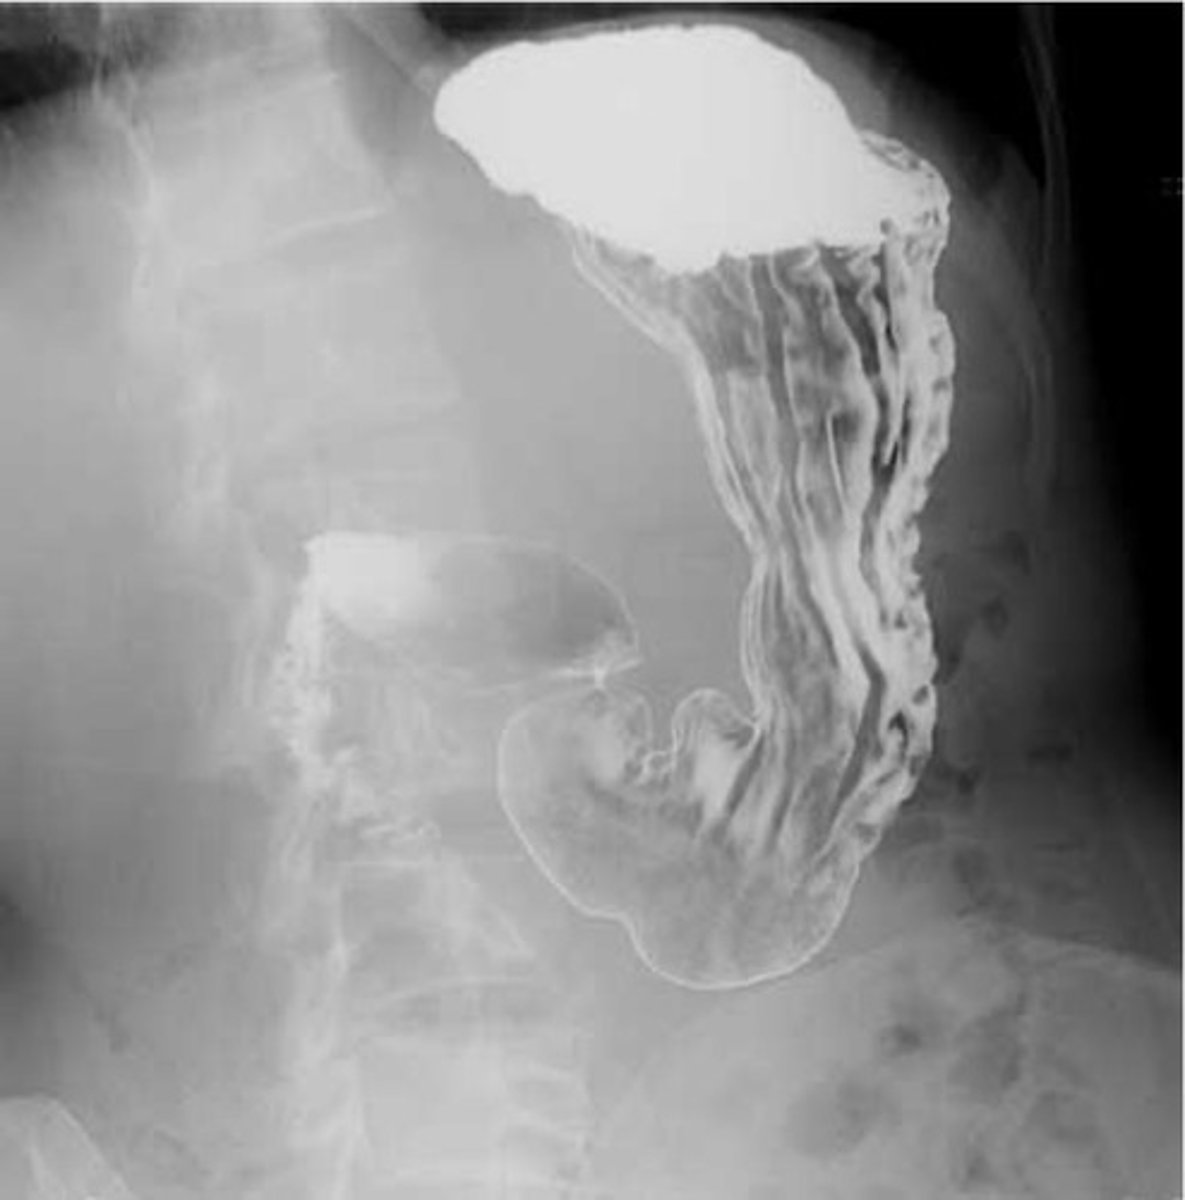

Normal barium swallow

Normal barium swallow (pic 2)